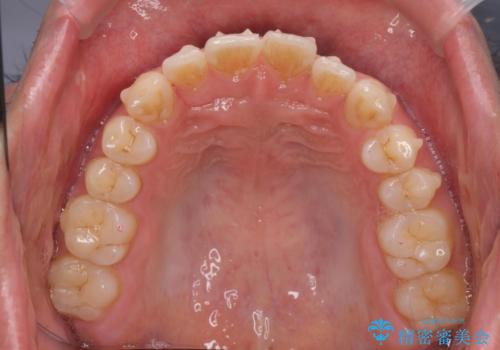

前歯が気になる。インビザラインライト

- 前歯が気になるとの事で来院。

矯正を希望されたが費用と時間を抑えたいとの事でインビザラインライトで矯正を行いました。(奥歯の位置関係はほぼ変えない)

前歯が綺麗に並び大変満足して頂けました。